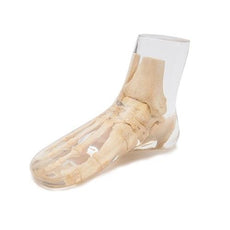

This X-Ray part phantom gives the unique opportunity to take x-ray images of single body parts again and again. The Phantom includes real human bones and allows taking real x-ray images. The model is perfect for schools and education, but also for medical technicians since the same bones can be x-rayed again and again in different settings without the danger of harming a patient. The bones are embedded

X-Ray Phantom Elbow, Transparent

This X-Ray part phantom gives the unique opportunity to take x-ray images of single body parts again and again. The Phantom includes real human bones and allows taking real x-ray images. The model is perfect for schools and education, but also for medical technicians since the same bones can be x-rayed again and again in different settings without the danger of harming a patient. The bones are embedded in transparent plastic. This phantom is handmade and unique. It may differ in size and shape. Due to production technology there may be discoloring and cracks inside the phantom. This is related to production and is no lack of quality. This phantom is only sold against a proof of medical use.

Part of upper and lower arm.

Including a transport and storage case.

Also available in Transparent Version.